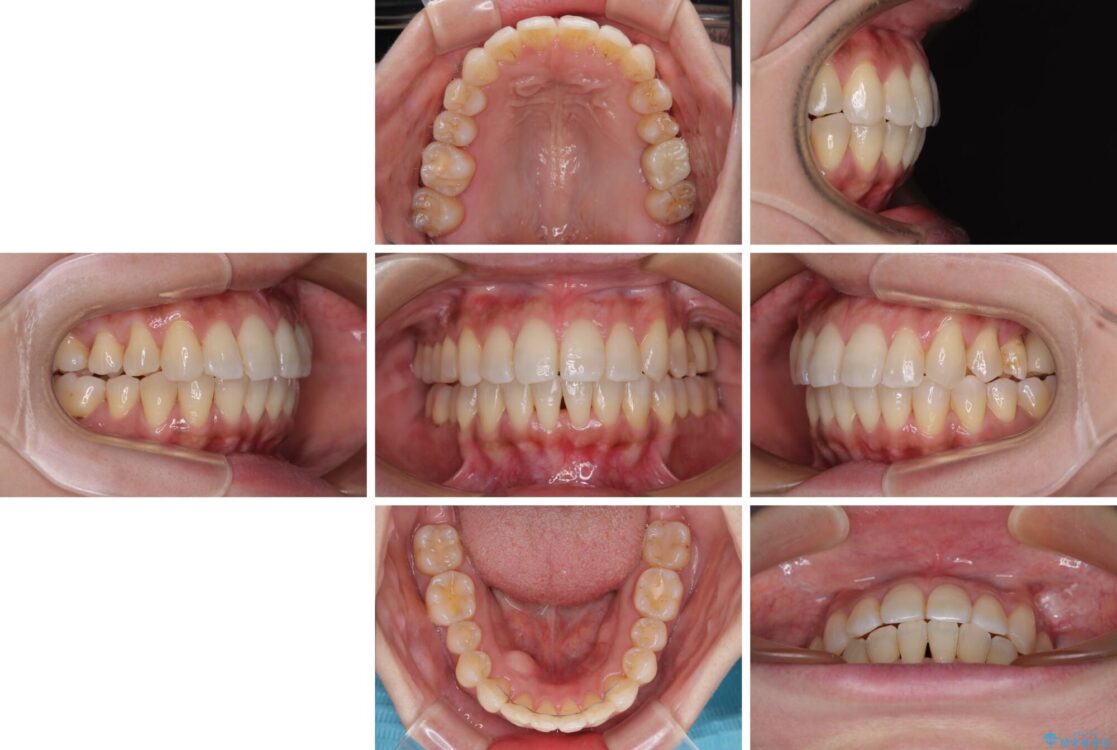

全体的なデコボコと、以前抜歯した歯のスペースを閉じた部分が気になるとのことで来院された患者様です。

左上第一大臼歯を抜歯した際に、スペースを閉じたそうですが、歯が傾斜してものが挟まって不快とのことでした。

インビザライン矯正で全体の歯列と整えるとともに、左上第一大臼歯部にはスペースを作り、インプラントによる補綴治療を行うこととしました。

治療前

• インビザラインによる矯正治療と奥歯のインプラント治療 治療前画像